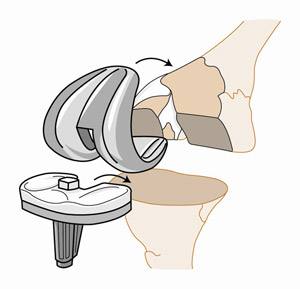

此时只能行全膝关节置换手术,并配合骨重建,重新换一个完整好用的人工关节。自体本身的关节,已经像一个千疮百孔的废胎,不能使用了。

人工膝关节手术

同时因为骨缺损,在原有关节置换步骤中,要进行植骨。对于比较复杂的病例,可以通过术前3D扫描获取解剖及结构学数据,定制符合缺口大小的骨植入物,将原本缺损的部分,填充起来,以增加人工关节的稳定性,延长使用寿命。